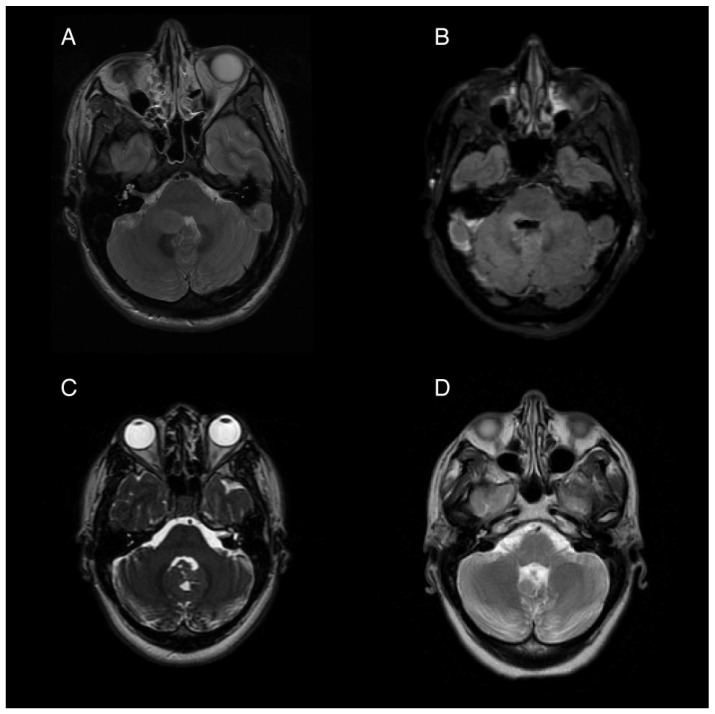

A 35-year-old woman presented to the hospital with a 2-day history of nausea, vomiting, and headaches. Neurological examination showed diffuse hyperreflexia and subtle right-sided dysdiadochokinesia. Imaging revealed an ovoid, non-enhancing expansile lesion in the right cerebellar hemisphere measuring 1.9 × 1.5 cm, affecting the right middle cerebellar peduncle and extending through the fourth ventricle (Figure 1A). Stereotactic biopsy followed by a gross total resection was performed, and the histology was consistent with pilocytic astrocytoma. An activating PTCH1 mutation was found in next generation sequencing, with the medulloblastoma tumor type confirmed by DNA methylation profiling.

Following tumor resection, the patient developed an ataxic gait, right upper extremity dysmetria, an extraocular “one and a half syndrome,” nausea, and vomiting. For two months post-operatively, the nausea was controlled with ondansetron, 4 mg three times daily, and promethazine, 12.5 mg every 6 h as needed for breakthrough events. Four months post-operatively, she started to experience intractable nausea and vomiting unresponsive to ondansetron and promethazine. She experienced frequent episodes of vomiting without provocation, as well as nausea and vertigo that sometimes, but not always preceded the vomiting. Her ability to participate in rehabilitation was severely limited by her intractable and unpredictable episodes of moment-to-moment nausea and vomiting. Regimens including oral granisetron, a granisetron patch, and olanzapine in combination provided incomplete relief. A trial of oral aprepitant for 3 days in combination with oral granisetron resulted in a significant improvement for about 1 week, but the symptoms returned. Her refractory vomiting four months after surgery was attributed to localized damage to the area postrema, evidenced by the post-operative edema at the base of the fourth ventricle seen on post-operative imaging (Figure 1B).

A 26-year-old woman presented for management following gross-total resection of a medulloblastoma, WNT-activated subtype, WHO grade 4 affecting her cerebellar vermis (Figure 1C). After the surgery the patient began experiencing daily (usually at least twice per day) episodes of sudden vomiting. These episodes were unrelated to meals and occurred without concurrent symptoms of vertigo or nausea. She had considerable anxiety with respect to her vomiting, which contributed to poor nutritional intake and a 14 kg weight loss in the month following her surgery. While the remainder of her neurological exam was mostly normal, she was also experiencing significant fatigue, dyspnea, and a sensation of instability without frank vertigo, requiring her to push a wheelchair for gait assistance.

Her episodic vomiting was attributed to APS caused by partial resection of the inferior cerebellum and an irritation of the dorsal medulla which was shown on imaging (Figure 1D). Notably, she did not have other symptoms of central vestibulopathy, particularly vertigo. Her vomiting was neither related to episodic vertiginous symptoms nor associated with body position or movement. She was initially started on a course of granisetron and aprepitant for a 5-day trial, which resulted in a reduction in her episodes of vomiting, but she then experienced a return of the vomiting episodes after 7 days. After this trial, treatment with weekly netupitant and palonosetron (combination antiemetic capsule) was initiated. She had a near complete resolution of her vomiting while on weekly netupitant and palonosetron.